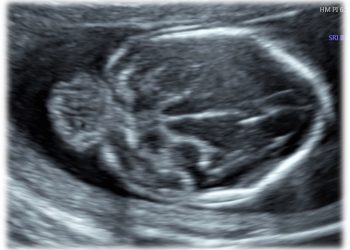

Cari soci, finalmente online le soluzioni dei casi del mese di Giugno!!! Grazie a Valentina D'Ambrosio e Alba Piras!! Caso...